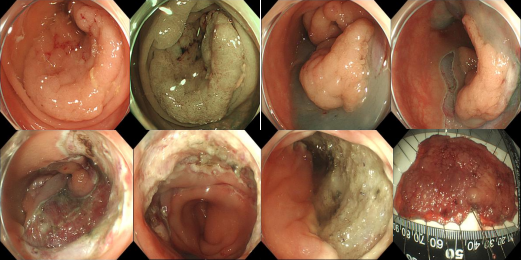

消化内科编制床位141张,年门诊平均就诊量约十万余人次,出院约6000余人次,内镜诊疗60000余人次,手术或治疗4千余例。我院地处川东北地区,长期收治不明原因腹水、不明原因消化道出血、不明原因腹痛、急性重症胰腺炎、肝硬化伴严重并发症及消化道大出血等疑难危急重症病人。作为川东北地区消化系统内科治疗的标杆,消化内科一直致力于示范和推广高水准的消化道诊疗技术,为提高诊疗技术,为广大患者提供更好的服务,我科购进了奥林巴斯小探头超声内镜、纵轴线阵扫描超声胃镜、奥林巴斯290色素放大内镜(NBI)、十二指肠镜、富士7000放大内镜、富士双气囊小肠镜等内镜下诊疗的高端设备。消化内科极其重视消化道肿瘤的早诊早治及消化内镜下一系列医疗技术,开展了EMR、 ESD、STER、POEM、EUS及内镜下止血等手术。同时,还大力开展消化放射介入治疗如ERCP等多项介入技术。消化内科联合急诊医学科、介入科、普外科等多科建立危险性消化道出血 MDT 团队,建立“危险性上消化道出血救治区域中心”,7×24 小时绿色通道,提供全面、优质诊疗方案,缩短危险性消化道出血急诊救治时间,大大提高了患者生存率。在临床工作中努力深化亚专科和各专业组建设,各专业组通过进修学习及各类学术交流、病例研讨等活动,不断提升团队整体实力,为患者提供更精准、更专业的医疗服务,努力在医学亚专业领域内实现新的突破与飞跃。

ESTD治疗多灶性复发型食管早癌

ESD治疗超低位大面积直肠早癌

STER治疗食管固有肌层肿瘤